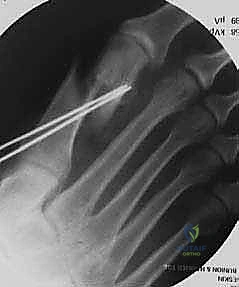

الخطوة الخامسة: التثبيت الداخلي القوي (Rigid Fixation)

لضمان عدم تحرك العظام أثناء فترة الالتئام، يتم تثبيت القص العظمي باستخدام مسامير تيتانيوم طبية متطورة (عادة مسمارين). تُستخدم مسامير ذات ضغط ذاتي وبدون رؤوس بارزة (Headless compression screws) بحيث تنغرس بالكامل داخل العظم ولا تسبب أي تهيج للأنسجة المجاورة، ولا تحتاج لإزالتها مستقبلاً.

إدخال أسلاك التوجيه (K-wires) لتثبيت العظم مؤقتاً والتأكد من الوضعية الصحيحة باستخدام جهاز الأشعة السينية داخل غرفة العمليات (C-arm) قبل وضع المسامير النهائية.

المسامير التيتانيومية المتقدمة توفر ثباتاً هائلاً، مما يسمح للمريض بالبدء في تحميل الوزن على كعب القدم في وقت مبكر جداً بعد الجراحة.